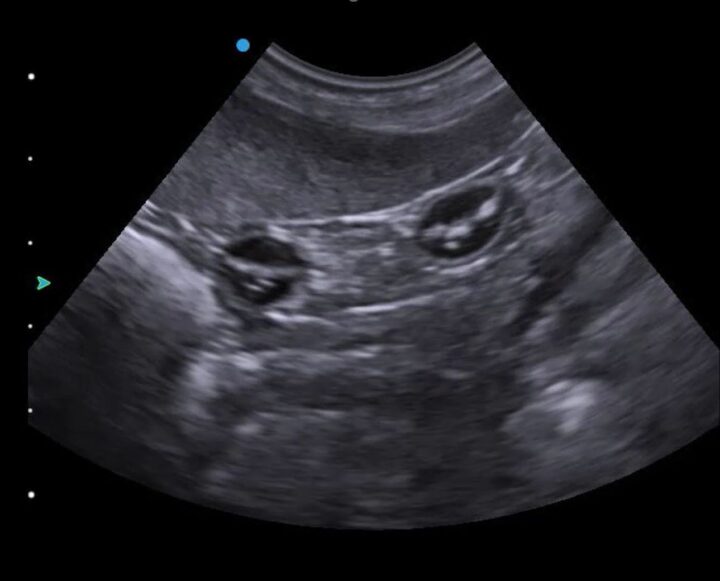

Intestines or gestation sacs? Manipulating the imaging plane

Once you have identified and looked around the bladder and as you begin to move your transducer cranially, you will encounter either more gestation sacs or the intestines (Figure 2) in the “normal” bitch or queen. Intestines are one of the great pitfalls of pregnancy scanning and are mistaken for gestation sacs more often than you might care to believe. The key is to rotate your transducer 90 degrees to confirm whether the circular structure you are seeing is indeed spherical (ie an early gestation sac).

If you are an experienced user of ultrasound, this will be easy and intuitive. But if you are new to ultrasound, this is a skill that is worth practising at every opportunity, as you will use this same movement to image the long and short axis of the foetus and almost every structure and organ you examine using ultrasound.